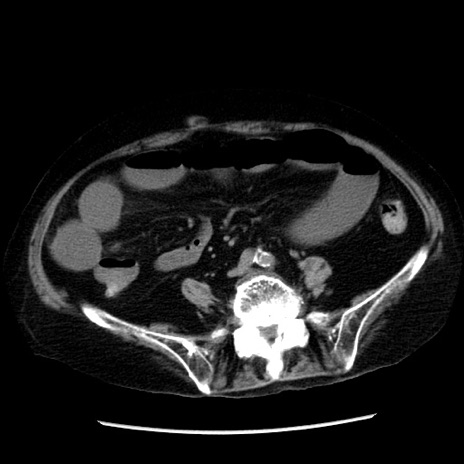

症例14(横断像)

【症例】 90歳代女性

【主訴】 腹痛・嘔吐

【現病歴】今朝から左側腹部痛を認めた。 経過観察していたが、嘔吐を認めたため来院。

【既往歴】 子宮癌術後

【身体所見】 意識清明、BP 127/54mmHg、P 98bpm Sp02 95%(RA)、BT 35.8°C、腹部平坦・軟腸ぜん動音聴取良好、右下腹部圧痛(+) 反跳痛なし

【データ】WBC 9800、CRP 0.46